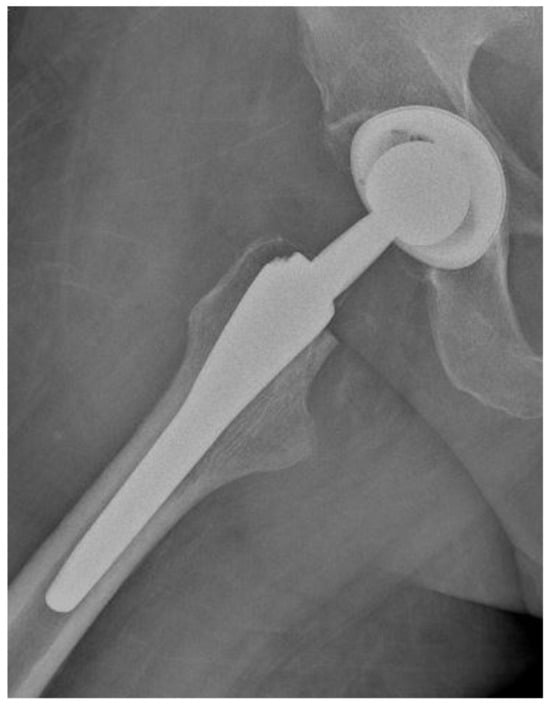

Of the 84 patients enrolled in this study, 44 patients (52.4%) received a THA with a straight stem (group A) (Figure 1 and Figure 2) and 40 patients (47.6%) received a THA with an anatomical stem (group B) (Figure 3 and Figure 4).

Figure 1.

Antero-posterior X-rays view of a total hip arthroplasty with straight stem (group A).

Figure 2.

Axial X-rays view of a total hip arthroplasty with straight stem (group A).